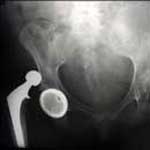

The ASR Hip Implant System is a metal-on-metal hip implant made of chromium and cobalt, consisting of a cup that’s implanted into the hip with a ball joint that connects to the leg. It is believed that many of the DePuy hip replacement complications linked to the DePuy ASR XL Acetabular hip implant are caused by wearing of the metal components, which can allow metal shavings to make their way into patients’ bloodstreams, leading to tissue breakdown, bone loss, and even the formation of non-cancerous tumors. The shedding of metal shavings can cause cobalt poisoning, a disorder that, if left untreated, can put patients at risk of tinnitus (ringing in the ears), vertigo, deafness, blindness, optic nerve atrophy, convulsions, headaches, peripheral neuropathy, cardiomyopathy, and hypothyroidism.